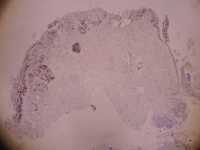

女39岁宫颈活检HPV53HPV58阳性 CIN2?

免疫组化分别是P16 Ki67

考虑为CIN2累腺

HSIL累腺。